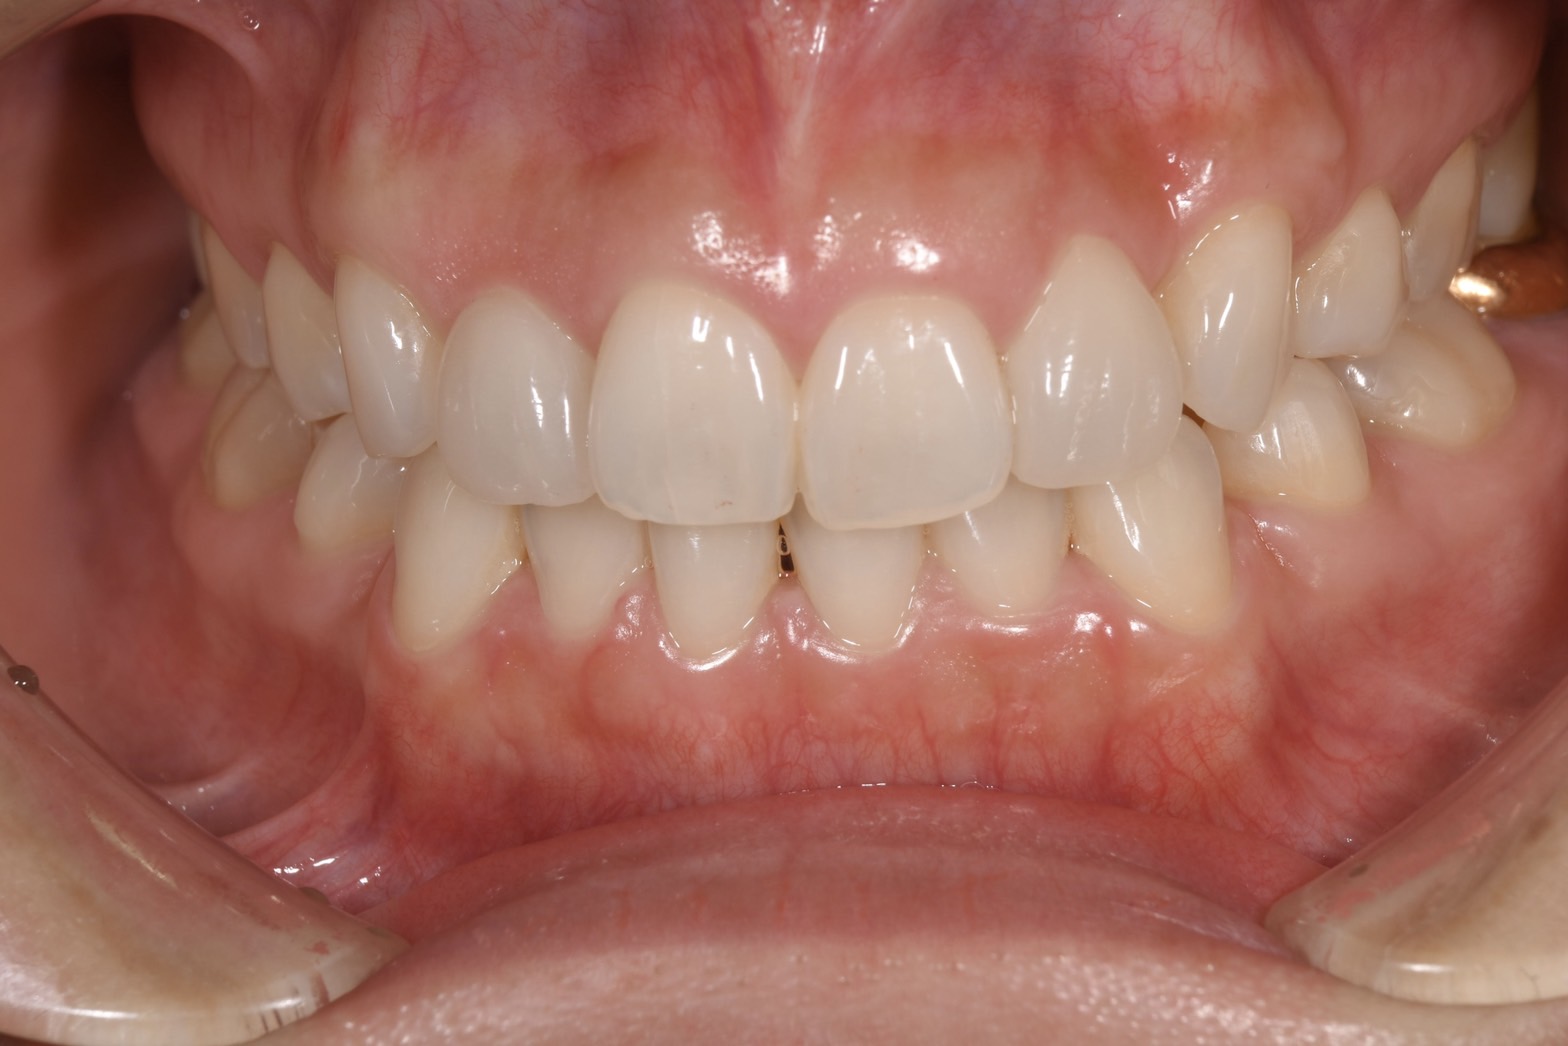

• ノンクラスプデンチャー

ノンクラスプデンチャー